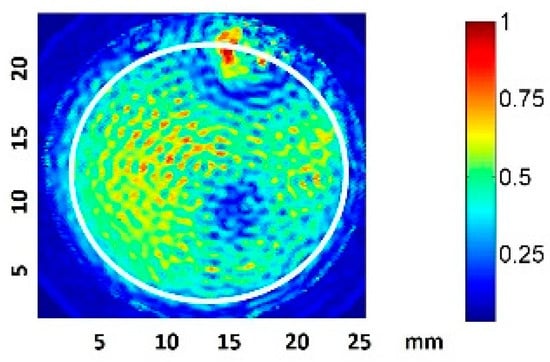

3.1. Ultrasound Field Characterization of the Culture Wells